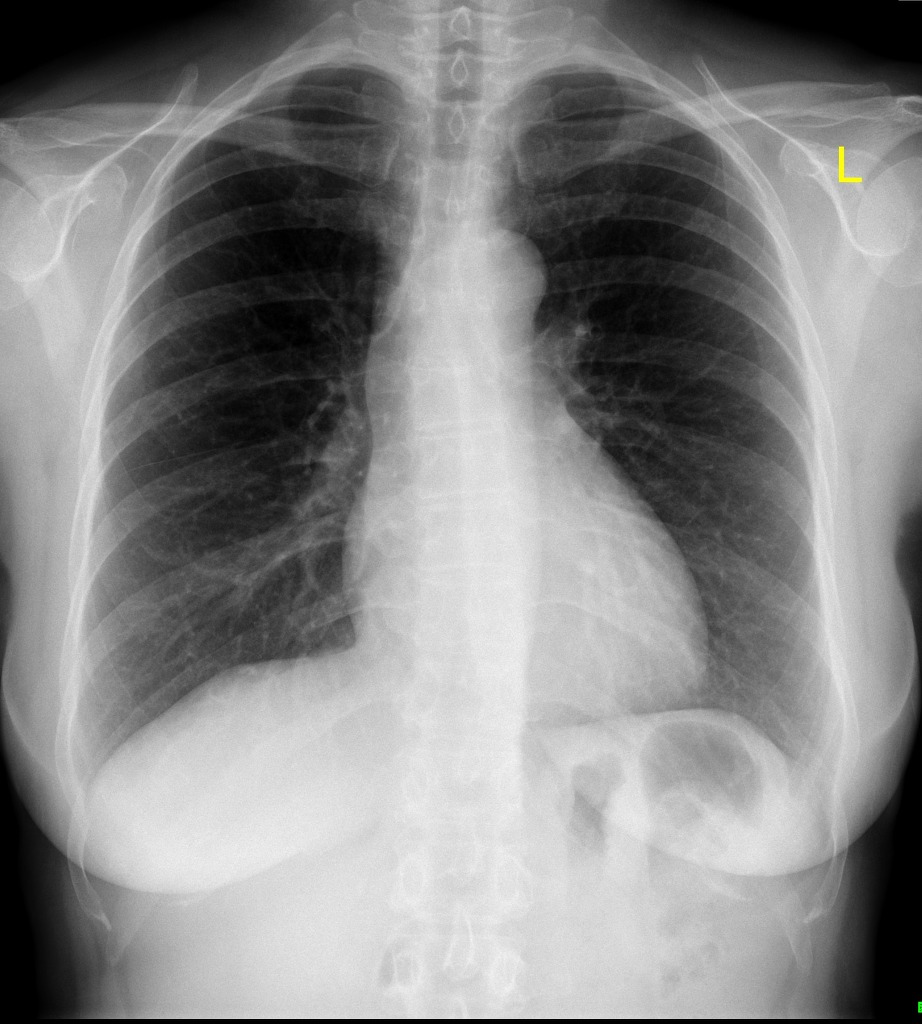

Faça a associação do quadro anterior à radiografia de tórax (sem alterações) à seguir:

- Abdome superior e diafragma: presença de bulha gástrica, seios costofrênicos livres, diafragma direito um pouco mais alto que o diafragma esquerdo.

- Parede torácica: avaliar as partes moles, integridade de mamas, cavos, axilas, fossas supraclaviculares e músculos do tórax.

- Ossos do tórax: analisar arcos costais, coluna torácica, escápulas clavículas, esterno e números proximais.

- Cavidades pleurais: espaços pleurais em estado normal são virtuais.

- Pulmões: à direita, tem 3 lobos e 2 fissuras e à esquerda, 2 lobos e 1 fissura. Avaliar trama vascular, hilo pulmonar, árvore traqueobrônquica (a direita é mais curta e verticalizada) e ângulo da carina.

- Mediastino: no pré-vascular (anterior), avaliar timo, gordura e linfonodos, no visceral (médio), avaliar traqueia, esôfago, linfonodos, coração e vasos e no paravertebral (posterior), avaliar partes moles e coluna torácica.